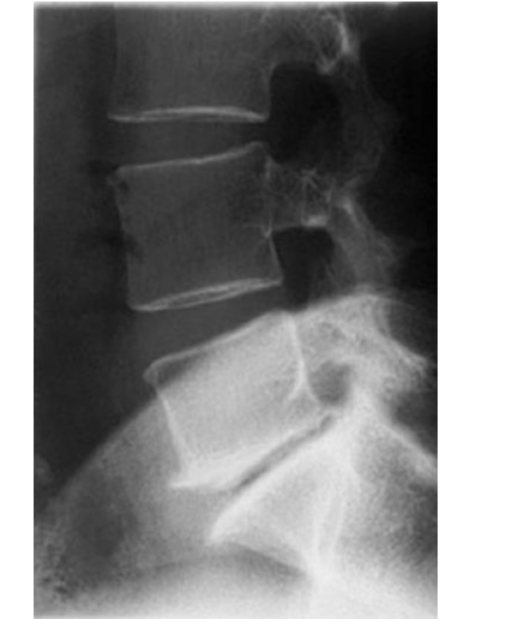

Discopathie dégénérative L5-S1

pincement discal

Ostéophytes antérieurs